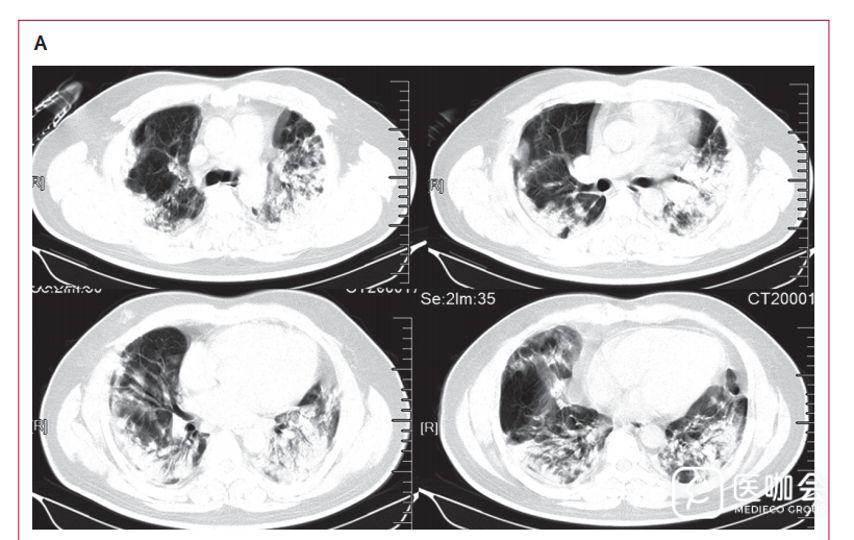

下图3是胸部CT的结果,分为ABC三张图。

B是在症状开始8天时,一位年龄53岁的女性胸部横面CT显示双侧磨玻璃状样变和亚段实变区。